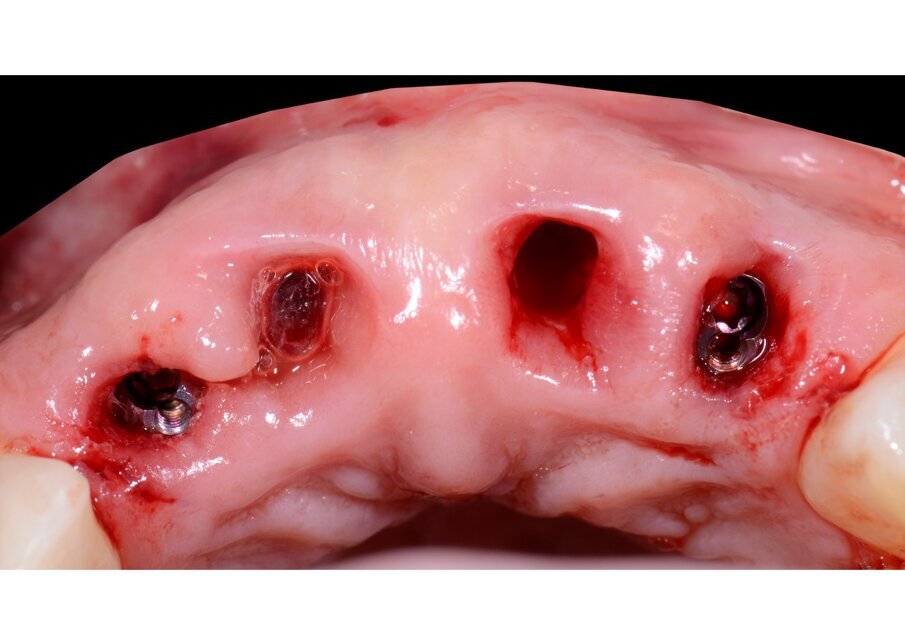

All’esame clinico presenta i quattro incisivi superiori malposizionati, con diastema per evidenti problemi parodontali. Perdita importante di supporto parodontale, presenza di tasche superiori a 6 mm, mobilità di tipo 2/3 su tutti i quattro elementi (Figg. 1-4).

Il nostro obiettivo è quello di riuscire a dare alla paziente un provvisorio immediato nell’arco di due ore. Questo diventa possibile perché abbiamo utilizzato un flusso digitale fin dall’inizio. In laboratorio vengono realizzate la dima chirurgica (Figg. 16, 17), la dima protesica (Fig. 18) e anche il provvisorio (Figg. 19-21) che contiene delle alette di riposizionamento. Il tutto gestito con modelli digitali sui quali saremo in grado di funzionalizzare il provvisorio post-chirurgico (tecnica DIL). In un caso come questo se utilizziamo un flusso digitale possiamo evitare subito dopo la chirurgia di rilevare un’impronta degli impianti inseriti. Infatti, utilizziamo una dima chirurgica che ci faciliterà le fasi di intervento. La dima ci consentirà di non fare lembi e nessuna incisione di rilascio (Fig. 22), dopo aver inserito gli impianti (BLX Straumann) (Figg. 23-31) e aver controllato il loro alloggiamento, inseriamo sugli stessi dei transfert da impronta (Fig. 32).

Fig. 31 - Visione occlusale impianti inseriti.

Fig. 32 - Transfert avvitati sugli impianti.